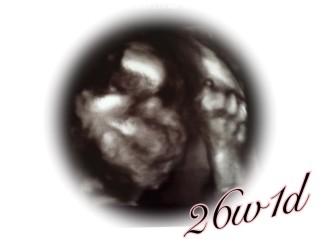

写真:26w1d:やんさん:目が開いてて!

割としっかりお顔が見れました❀.(*´▽`*)❀. 先生に「しっかりお鼻も高いね♬︎」と言われました! 今まで次男に似ていると思っていましたが、今回のエコーでは長男にも長女にも似ています(o´∀`o) BPD6.4cm、FL4.5cm、お腹周りが少し大きめの推定体重940gの男の子です(๑・ỏ・๑) 可愛い~!楽しみで仕方ありません(っ ॑꒳ ॑c) ママは悪阻がまだ終わらず毎日辛いです・・・